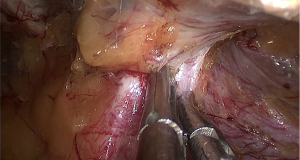

In step 3, the silica gel incision seal sleeve of the single-hole device is installed below the aponeurotic layer of the incision (Figure 4). The silica gel sealing sleeve of the Iconport single-port device is inserted under the posterior rectus abdominis sheath. As long as the silica gel sheath is installed below the aponeurotic layer of the incision, the operation could commence smoothly, even if there is not enough space for the silica gel sheath to open naturally. As the camera is inserted into the incision, the silica gel seal is held open, and the layers of tissue are identified in the field of view (Figure 5). The superficial tissue of the preperitoneal fascia is cut transversely along the deep surface of the aponeurosis using an electrocoagulation device, and the space within the preperitoneal space is gradually increased (Figure 6).